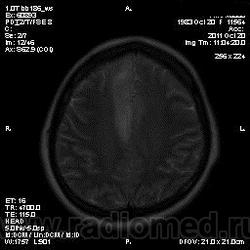

Эта же пациентка... Июль 2011 года....

В анамнезе есть зацепки на энцефалит?Мне ни разу не встречался, поэтому умничать не буду.

мне кажется больше похоже на диффузную глиальную опухоль. Для герпетического нехарактерна локализация и характер контрастирования. Хотя конечно нет правил без исключений..

Евгений Второй, а медиобазальные отделы височных долей - по-моему излюбленная локализация герпетических энцефалитов... Да мне кажется, что серое и белое вещество в равной степени вовлечено в процесс...

а медиобазальные отделы височных долей - по-моему излюбленная локализация герпетических энцефалитов..

Абсолютно согласен, просто у меня не все картинки раньше загрузились и показалось, что все изменения в лобных долях и базальных ядрах. Снимаю свои возражения.